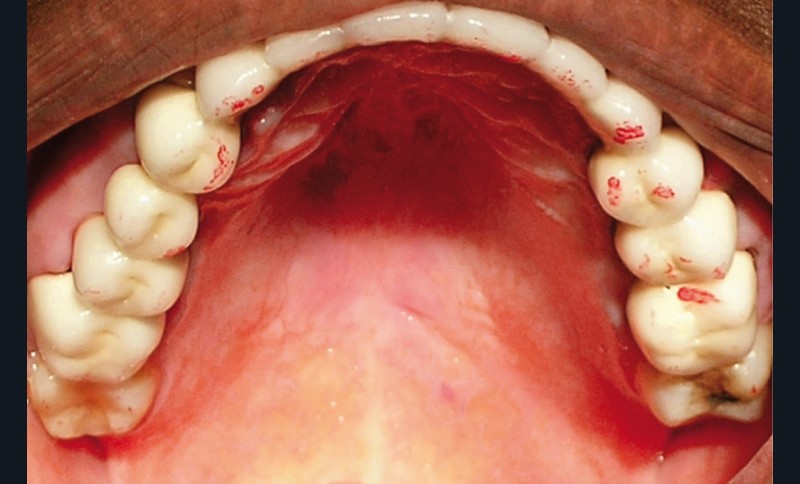

La patiente a été porteuse d’un bridge céramo-métallique de onze éléments au maxillaire pendant huit mois (fig. 1, 2), puis d’un bridge transitoire au maxillaire (fig. 3). Elle signale quelques rares épisodes de saignement probablement dus à l’irritation par la prothèse. Cette dernière se descelle couramment, créant ainsi un préjudice fonctionnel, esthétique et psychologique.

L’examen dentaire ne montre pas de mobilité dentaire. À l’arcade maxillaire, les dents 11, 14, 21, 22, 23 sont absentes. Les dents 13, 15, 24, 25 sont à l’état de racine (fig. 4). Nous notons des reconstitutions coronaires à l’amalgame sur les 26 et 16. À l’arcade mandibulaire, les dents 37, 36, 46, 47 sont absentes et une obturation coronaire à l’amalgame sur 38 est en place. Les bords libres du groupe incisivo-canin et les cuspides des prémolaires sont légèrement abrasés (fig. 5).